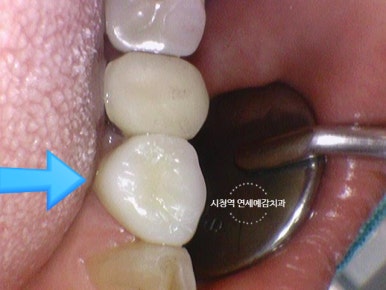

같은 치아의 전후 사진입니다.

위 사진을 보면 왼쪽사진에서 겉에서 보이는 충치가 있고

겉에서는 보이지 않고 엑스레이 상에서만 보이는 충치가 있었는데

실제로 치아를 파보면 같은 깊이를 팠을 때 겉에서 보이던 충치의 깊이보다

겉에서 안보이던 충치가 훨씬 더 깊고 상태가 심각함을 볼 수 있습니다.

충치가 있는 부분을 파내고 그 부분을 하얀색인 레진재료로 때우게 됩니다.

레진치료 전후